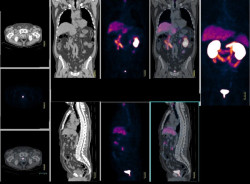

La cirugía es un tratamiento viable para los pacientes con cáncer de páncreas, especialmente tras la quimioterapia

Los pacientes con cáncer de páncreas en estadio II que reciben quimioterapia seguida de una intervención para eliminar la parte cancerosa del órgano, viven casi el doble de tiempo que los pacientes que reciben quimioterapia sola, según una nueva investigación publicada en línea en el `Journal of the American College of Surgeons`.